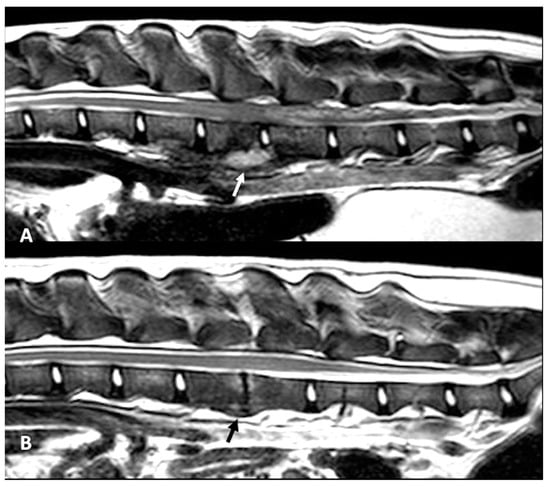

Follow-up MRI studies were performed (n = 13) from 2 to 5 months after treatment initiation, in 8/13 dogs conservatively treated (Figure 1D–F) and in 5/13 of the dogs surgically treated (Figure 2B and Figure 3E–G). Radiological improvement was noticed in all dogs, considering there were no signs of epidural material or soft tissue enhancement. Bone changes (osteoproliferation and mild contrast enhancement) were still present.

Figure 2. MRI T2-W sagittal plane at time of presentation (A) and follow-up at 4 months (B) in a dog with SEE surgically treated. On the intervertebral disk L3–L4 there is an infiltrative lesion also affecting the ventral paravertebral muscles and vertebral body of L3 (white arrow). The follow-up image (B) demonstrates the resolution of the paravertebral lesion and residual changes with new bone formation, loss of intervertebral space and mild vertebral marrow edema (black arrow).